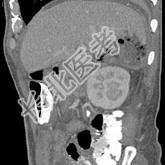

- 单项选择题男,44岁, 发热、右上腹痛半月,加重1天, 查体:右下肺呼吸音低, 影像检查如图,最佳诊断是 ( )

A、腹腔积液

B、膈下脓肿

C、肝包膜下出血

D、肝硬化腹水

E、肝癌